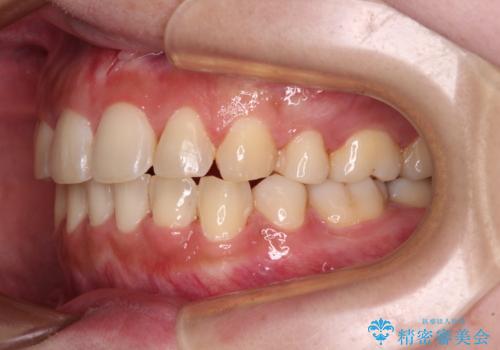

- 八重歯やデコボコをインビザラインで治療したいとのことで来院された患者様です。

インビザライン単体で治療を行うには叢生が強いと判断されたため、事前にワイヤー装置で抜歯矯正を行い、ある程度改善してからインビザラインにて仕上げていくこととしました。